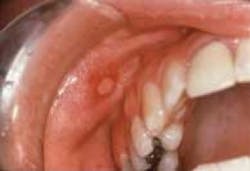

Figure 1: Minor RAS. Courtesy of Discus Dental, LLC.

Minor RAS may present as single or multiple lesions. They appear with acute onset and generally are less than 0.5 cm in diameter (see Figure 1). The ulcer is covered by a yellow fibrinous membrane and surrounded by an erythematous halo. Major aphthous lesions are less common, but these ulcers can be greater than 1 cm in diameter and considerably more painful. Clinically, major and minor RAS can both appear crateriform. The herpetiform type of RAS presents as multiple small ulcers that tend to coalesce. Unlike herpes infections, these ulcers are not preceded by vesicles and do not demonstrate virus-infected cells.